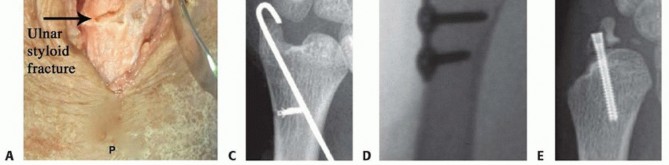

TECH FIG 4 • Ulnar styloid fracture fixation. A. The distal ulna is exposed at the ulnar styloid and a 3.5-mm drill guide is used to reduce the fracture and to pass K-wires. B. Anteroposterior (AP) radiograph of a tension band open reduction internal fixation (ORIF). C. Tension band construct with a suture anchor. D. ORIF with plate and screw construct. E. Loss of fixation using headless compression screw. A transverse (dorsal to volar) 2-mm drill hold is made proximally through the ulnar neck, and a 27-gauge wire is placed through the TFCC at its insertion on the ulnar styloid.A figure-of-eight bend is made, and one limb is passed volar to dorsal through the transverse bone hole, whereas the other is passed dorsal to volar.The wire is then twisted to tension, and the pins are bent and cut. The bent tips are pointed radially and driven into the styloid with a small bone tamp, capturing the wire ( TECH FIG 4B).Alternatively, after placing the pins through the ulnar styloid, a 2-0 suture anchor can be placed in the ulnar neck and the sutures passed in opposite directions around the styloid. The limbs are tied down to the medial ulnar shaft, and the pins are bent and cut as previously discussed ( TECH FIG 4C).Plate and screw construct may also be used for buttress effect, but implant prominence must be considered ( TECH FIG 4D).Headless compression screw fixation is advocated by some. We have noted frequent failure and malreduction with this technique. If screw fixation is used, bicortical fixation is recommended ( TECH FIG 4E).If the DRUJ is still unstable, proceed with radioulnar transfixation pinning. Wound closure, sterile dressings, and long posterior splint are applied.P.250PEARLS AND PITFALLS